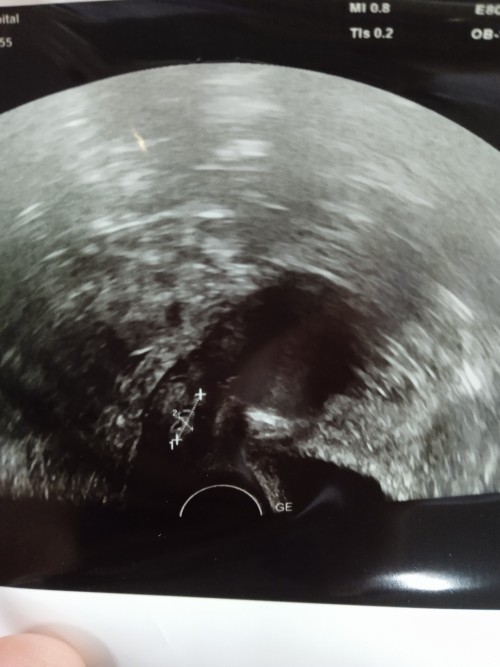

ถ้าขึ้นภายใน5 นาทีก้อท้องค่ะ อาจจะท้องอ่อนๆ อีกหนึ่งอาทิตย์ตรวจใหม่ บ้านนี้เคยตรวจละขึ้นขีดจางๆแบบหยด พอไปซาวด์ สรุปท้อง แต่ดันมีเลือดออก รอบนี้เลยไป โรงพยาบาล หมอซาวด์ช่องคลอดให้ หมอนัด อีกที17พ.ค ว่าน้องยังอยู่ไหม ตื่นเต้น ทั้งกลัว ท้อง สองค่ะ ถ้าแม่อยากรู้เร็วไปหาหมอเลยค่ะ